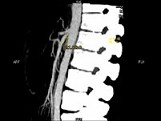

- 多项选择题女,24岁, 发作性肉眼血尿1年,实验室检查: 尿蛋白(-~+)、红细胞(1~2/HP),尿蛋白直立试验(+), CT扫描如图,下列说法正确的是 ( )

B、左肾静脉走行至肠系膜上动脉与腹主动脉间变细,近左肾处扩张

C、左侧肠系膜上动脉与腹主动脉夹角变小

D、左侧肠系膜上动脉与腹主动脉夹角增大

E、考虑为左肾静脉胡桃夹综合征